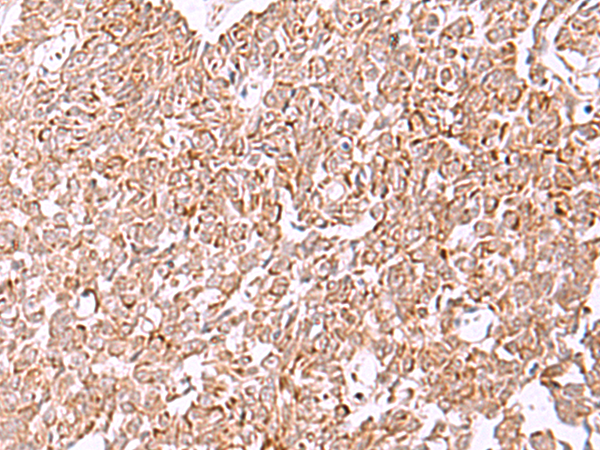

The image is immunohistochemistry of paraffin-embedded Human lung cancer tissue using P06762(IRX2 Antibody) at dilution 1/45. (Original magnification: ×200) |